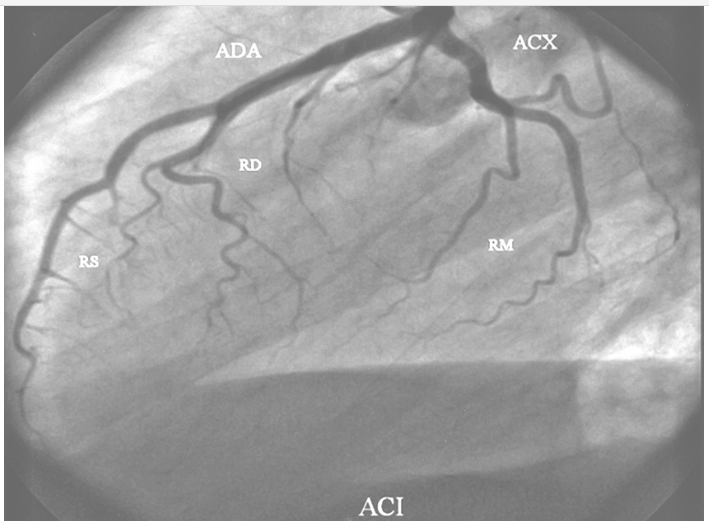

Arteria coronaria izquierda. Anatomía normal. ADA: Arteria descendente anterior; RD: diagonal de Rama; RS: Ramas septales; ACX: Arteria circunfleja; RM: Ramas marginales o laterales.